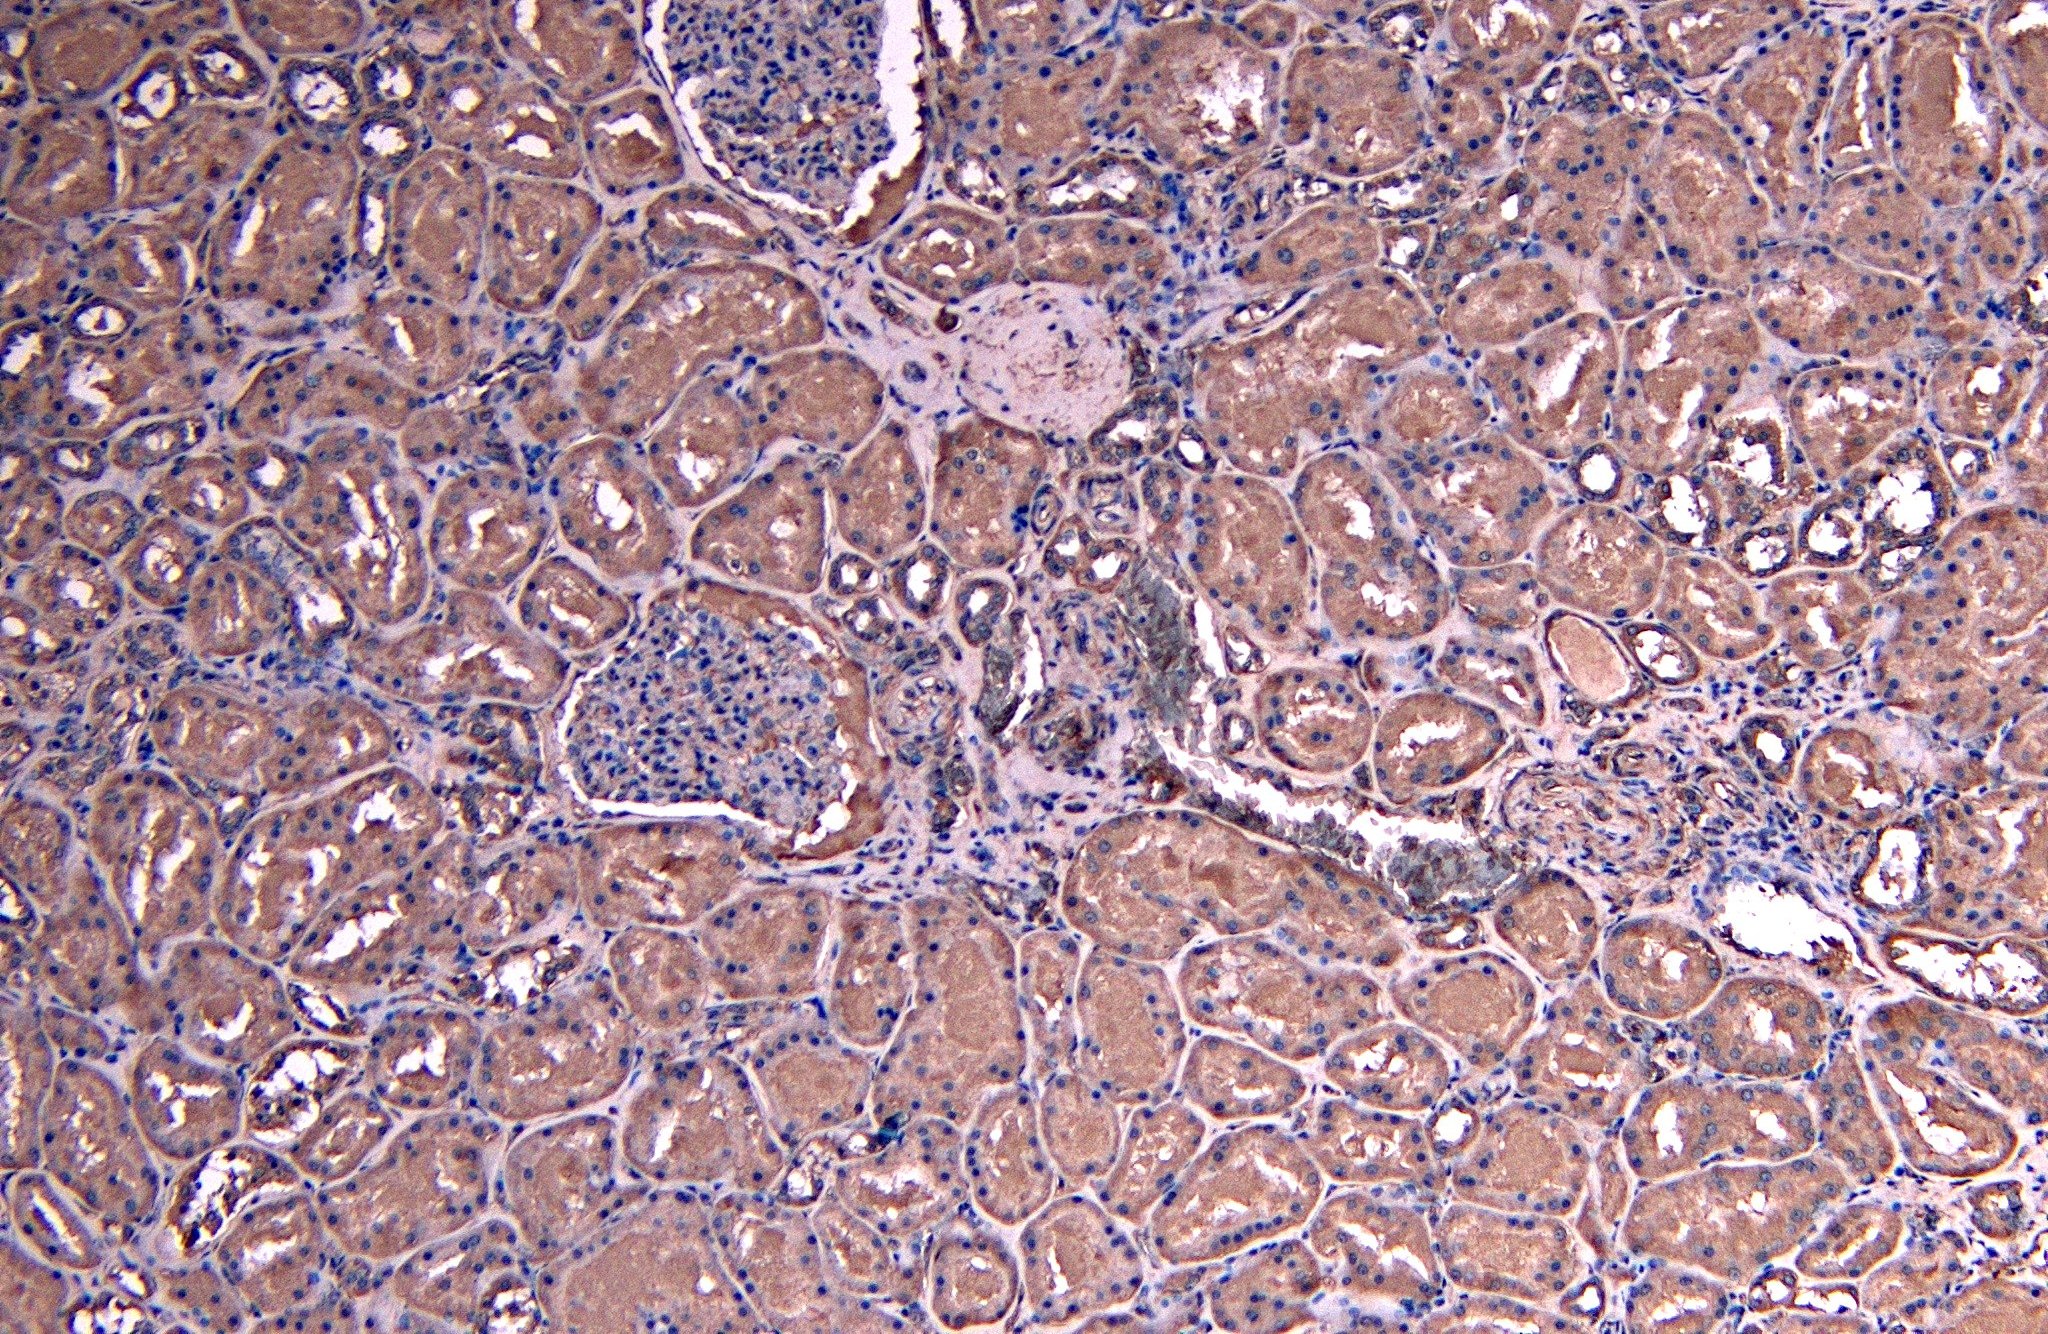

IHC Results Paraffin embedded Human Kidney. Recommended concentration: 8µg/ml. Paraffin embedded Mouse Kidney. Recommended concentration: 5-10µg/ml. | |